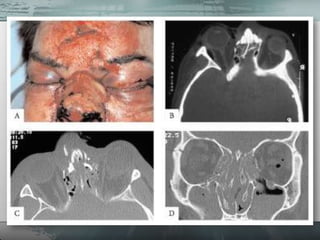

• 88.

• São fraturasresultantes de impactos com grande energia.

• 89.

• Apresentam aspecto clínico agressivo. • Alto custo financeiro de retorno do paciente ao convívio social. • Alto índice de sequelas

• 90.

• São tratamentos complexos. • Muitas vezes exigem diversas cirurgias. • Grande morbidade.

• 94.

CNF 94

• 103.

1 semana PO 1 ano PO